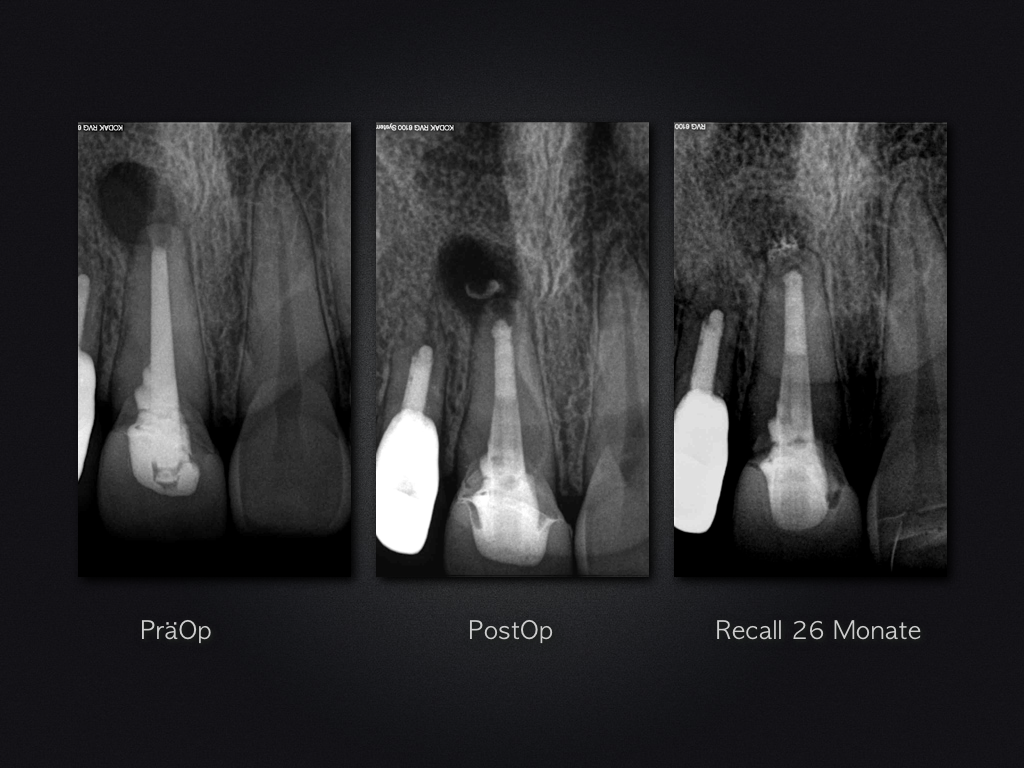

Und es heilt doch!